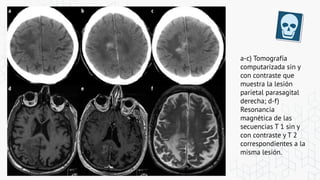

Neoplasica

a-c) Tomografía

computarizada sin y

con contraste que

muestra la lesión

parietal parasagital

derecha; d-f)

Resonancia

magnética de las

secuencias T 1 sin y

con contraste y T 2

correspondientes a la

misma lesión.

a-c) Tomografía computarizada siny con contraste que muestra la lesión parietal parasagital derecha; d-f) Resonancia magnética de las secuencias T 1 sin y con contraste y T 2 correspondientes a la misma lesión.